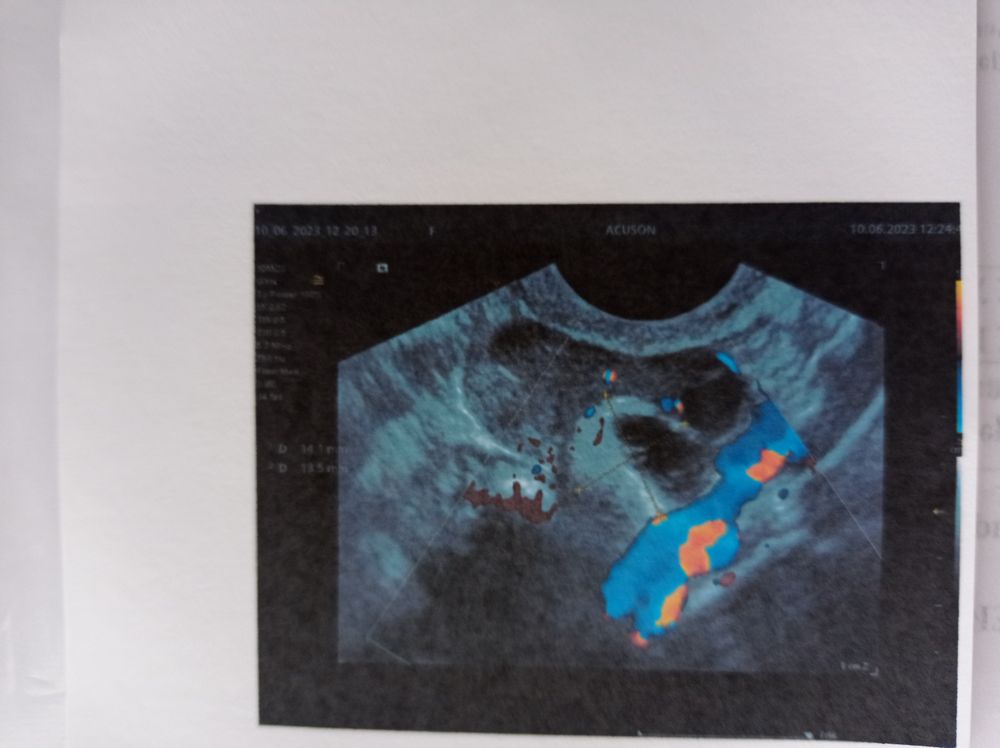

Добрый день, Ольга. Подскажите пожалуйста. Может функциональное образование яичника стать геморрагической кистой? Дермоидную кисту если она есть по УЗИ, обнаружили в 2021-2022 году, ранее по УЗИ данной кисты не было. Это невозможно правильно? Дермоидная киста врождённая. Сомнения какой вид кисты определили правильно. По результатам УЗИ 2018-2019 г. образований не было. В октябре 2021 г обнаружили функциональное образование левого яичника размерами 17*9*15 мм, в ноябре размеры 15*9*15 мм. В июне 2022 году функциональное образование левого яичника 10*12*9 мм. В сентябре 2022 г, результат УЗИ у другого специалиста дермоидная киста левого яичника 12,7*12,3*14,8 мм. и повторно УЗИ январь 2023 г. 15*14*17.8 мм. Последнее УЗИ 10.06.2023 г, в заключении: левый яичник геморрагическая киста с кальцификацией, в объеме 14 мм.